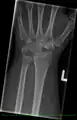

Shown is the right hand, palm down (left) and palm up (right).

Proximal: A=Scaphoid, B=Lunate, C=Triquetral, D=Pisiform

Distal: E=Trapezium, F=Trapezoid, G=Capitate, H=Hamate